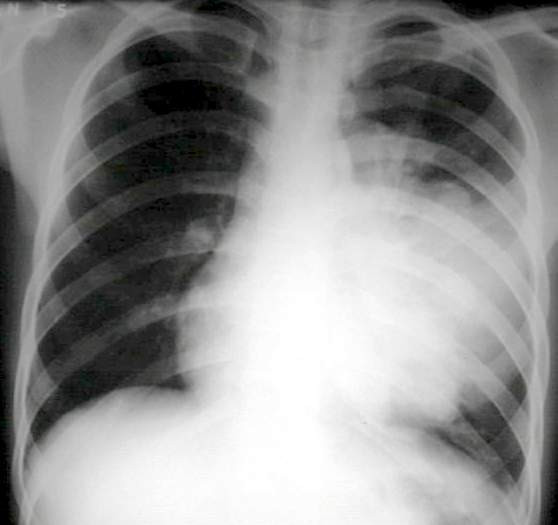

| 9. Viêm phổi: Ho và giảm cân có thể là chỉ báo về một bệnh nhiễm trùng nghiêm trọng do vi khuẩn gây ra, mà bình thường nếu hệ miễn dịch khỏe mạnh bạn không thể mắc. |